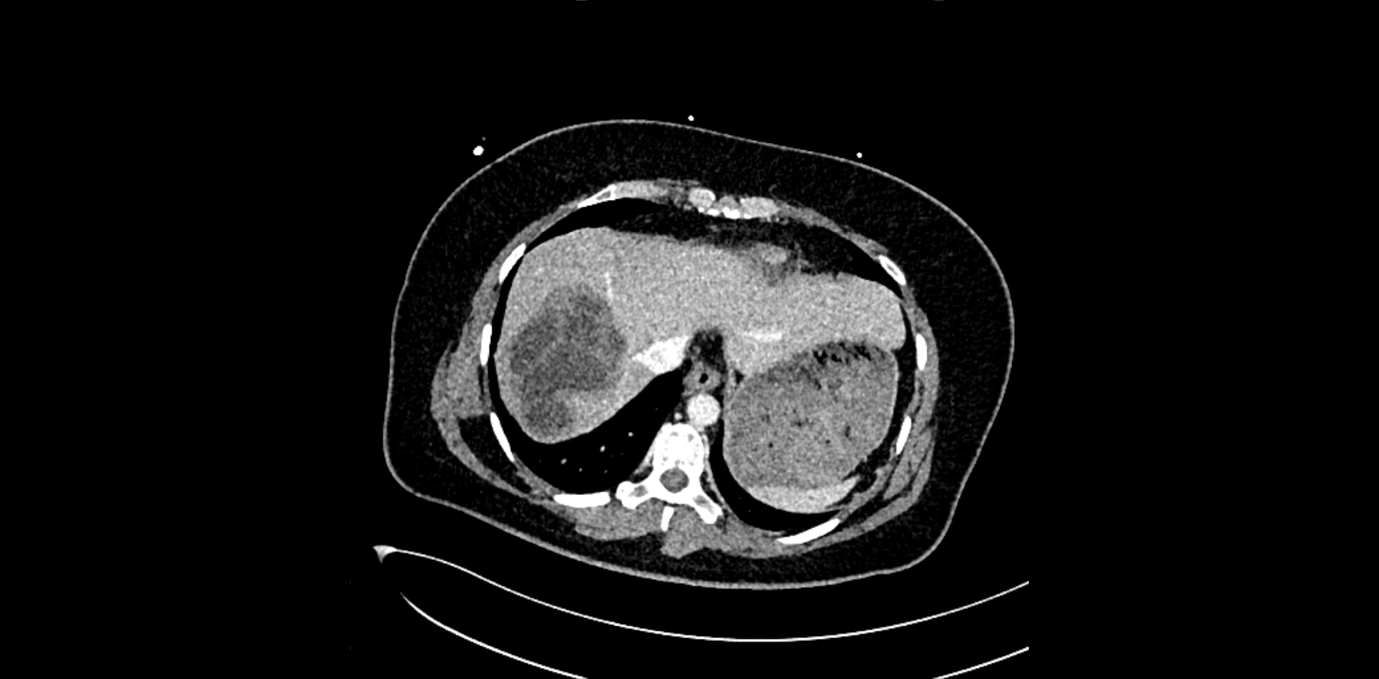

In der klinischen Untersuchung zeigt sich ein diskreter Sklerenikterus und ein leichter rechtsseitiger Oberbauchschmerz. Laborchemisch zeigen sich erhöhte Transaminasen sowie eine Bilirubinämie. Die Leukozyten und das C-reaktive Protein waren ebenfalls erhöht. In der orientierenden Sonographie bei dem Internisten zeigte sich eine ca. 16 cm messende echoarme, septierte Raumforderung, woraufhin die Patientin zur stationären Abklärung eingewiesen wurde. Bei der Aufnahme wurde eine Computertomographie des Abdomens durchgeführt.

In der CT-Untersuchung zeigte sich eine 16 x 14 cm messende, multilobulierte hypodense Raumforderung in den Lebersegmenten VII, VIII und VIa mit konsekutiver Cholestase im rechten Leberlappen. Die Pfortader und die Lebervenen waren offen. Die restlichen Organe waren unauffällig. Bei komplizierten Leberzysten wurde die Serologie für Echinokokkose abgenommen. Auf die gezielte Frage nach Kontakt zu Hunden und Füchsen hat Frau K. angegeben, dass sie drei Hunde auf dem Bauernhof hat. Der Echinokokken-IgG-Screening-ELISA war mit 47 U/ml positiv. Somit wurde die Diagnose einer Echinokokkose gestellt.